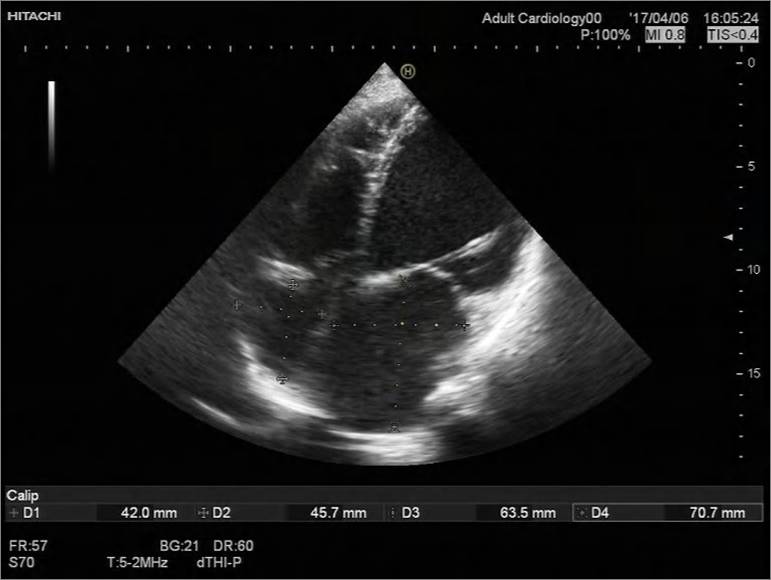

2017-4-7心超检查报告:

符合扩张型心肌病声像图改变:

◆1、左室壁运动弥漫性减弱 左心及右房大 ,EF 21%,左室缩末内径 76mm,舒末内径85mm。

◆ 2、二尖瓣前瓣瓣尖轻微对合错位并二尖瓣重度关闭不全(瓣环扩张所致)

◆3、 三尖瓣中度反流、主动脉瓣微量反流 左室收缩舒张功能减退 肺动脉高压(中度)